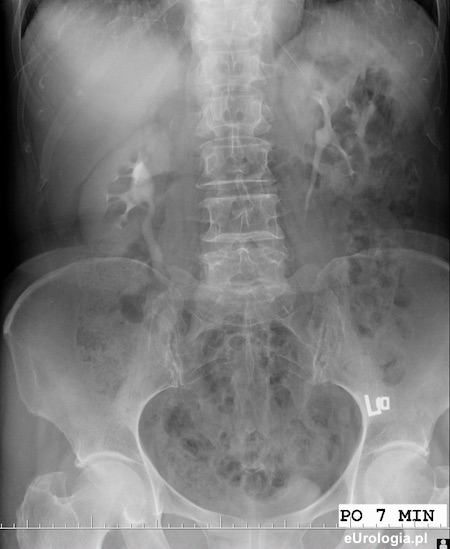

Zdjęcie urograficzne wykonane po 7 minutach od podania kontrastu. Widoczne układy zbiorcze nerek i górne odcinki moczowodów.